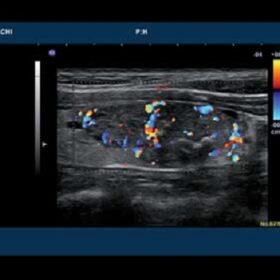

Ultrasound EUB-7500HV – Image Gallery

- dynamic Contrast Harmonic Imaging (dCHI)